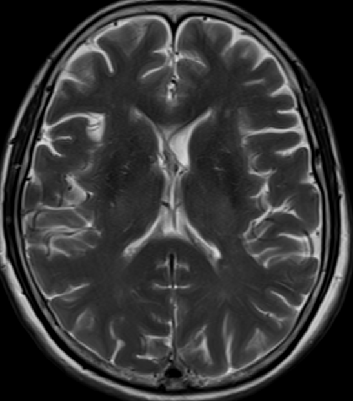

2013-5-16 MRI